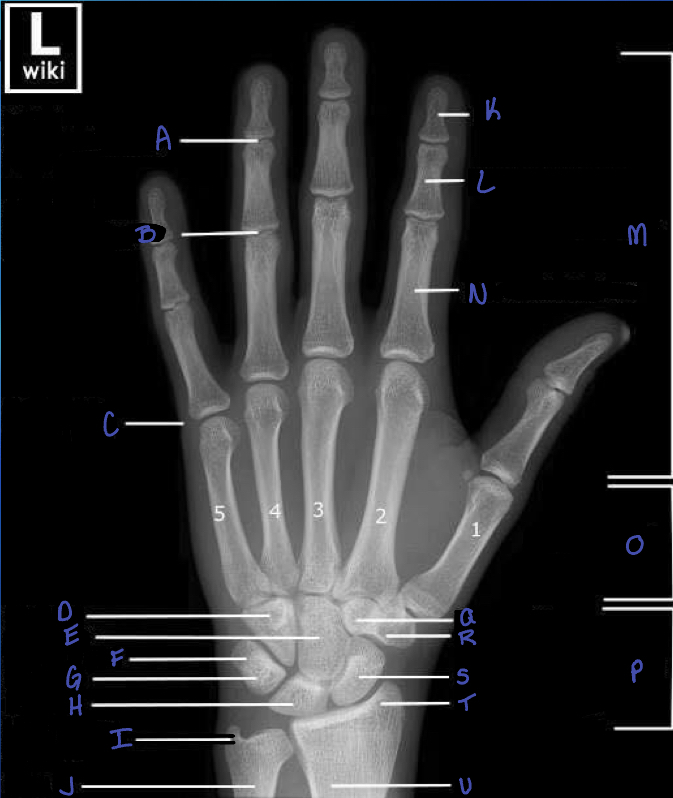

13

distal interphalangeal joint

14

proximal interphalangeal joint

15

metacarpophalangeal joint

16

hamate b

17

capitate b

18

triquetrium b.

19

pisiform

20

lunate b.

21

ulna styloid process

22

ulna

23

distal phalanx

24

middle phalanx

25

phalanges

What is M?

proximal phalanx

26

metacarpals

what is N?

carpals

What is P?

trapezoid b.

What is Q?

trapezium b.

What is R?

scaphoid b.

What is S?

radial styloid process

What is T?

radius

What is U?